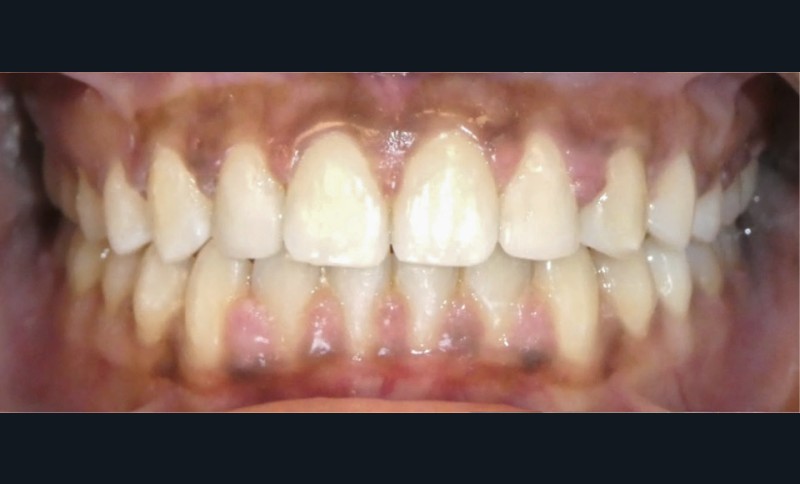

Diagnostic (fig. 1 et 2)

À l’examen extra-oral, la patiente présente un profil biprognathe associé à une Classe II squelettique modérée dans un contexte de normodivergence. L’angle naso-labial apparaît ouvert, le sillon labio-mentonnier est marqué et une prochéilie mandibulaire est observée. Le sourire se révèle disharmonieux, avec une faible visibilité des dents maxillaires.

À l’examen intra-oral, les arcades sont paraboliques, la courbe de Spee est normale. On remarque l’absence de la 23 sur l’arcade ainsi que la persistance de la 63. La patiente présente une Classe II partielle molaire et canine subdivision droite, ainsi qu’une insuffisance de recouvrement. Un léger encombrement incisif mandibulaire est présent, ainsi que des diastèmes maxillaires avec une dysmorphie dento-dentaire de 12 et 22.